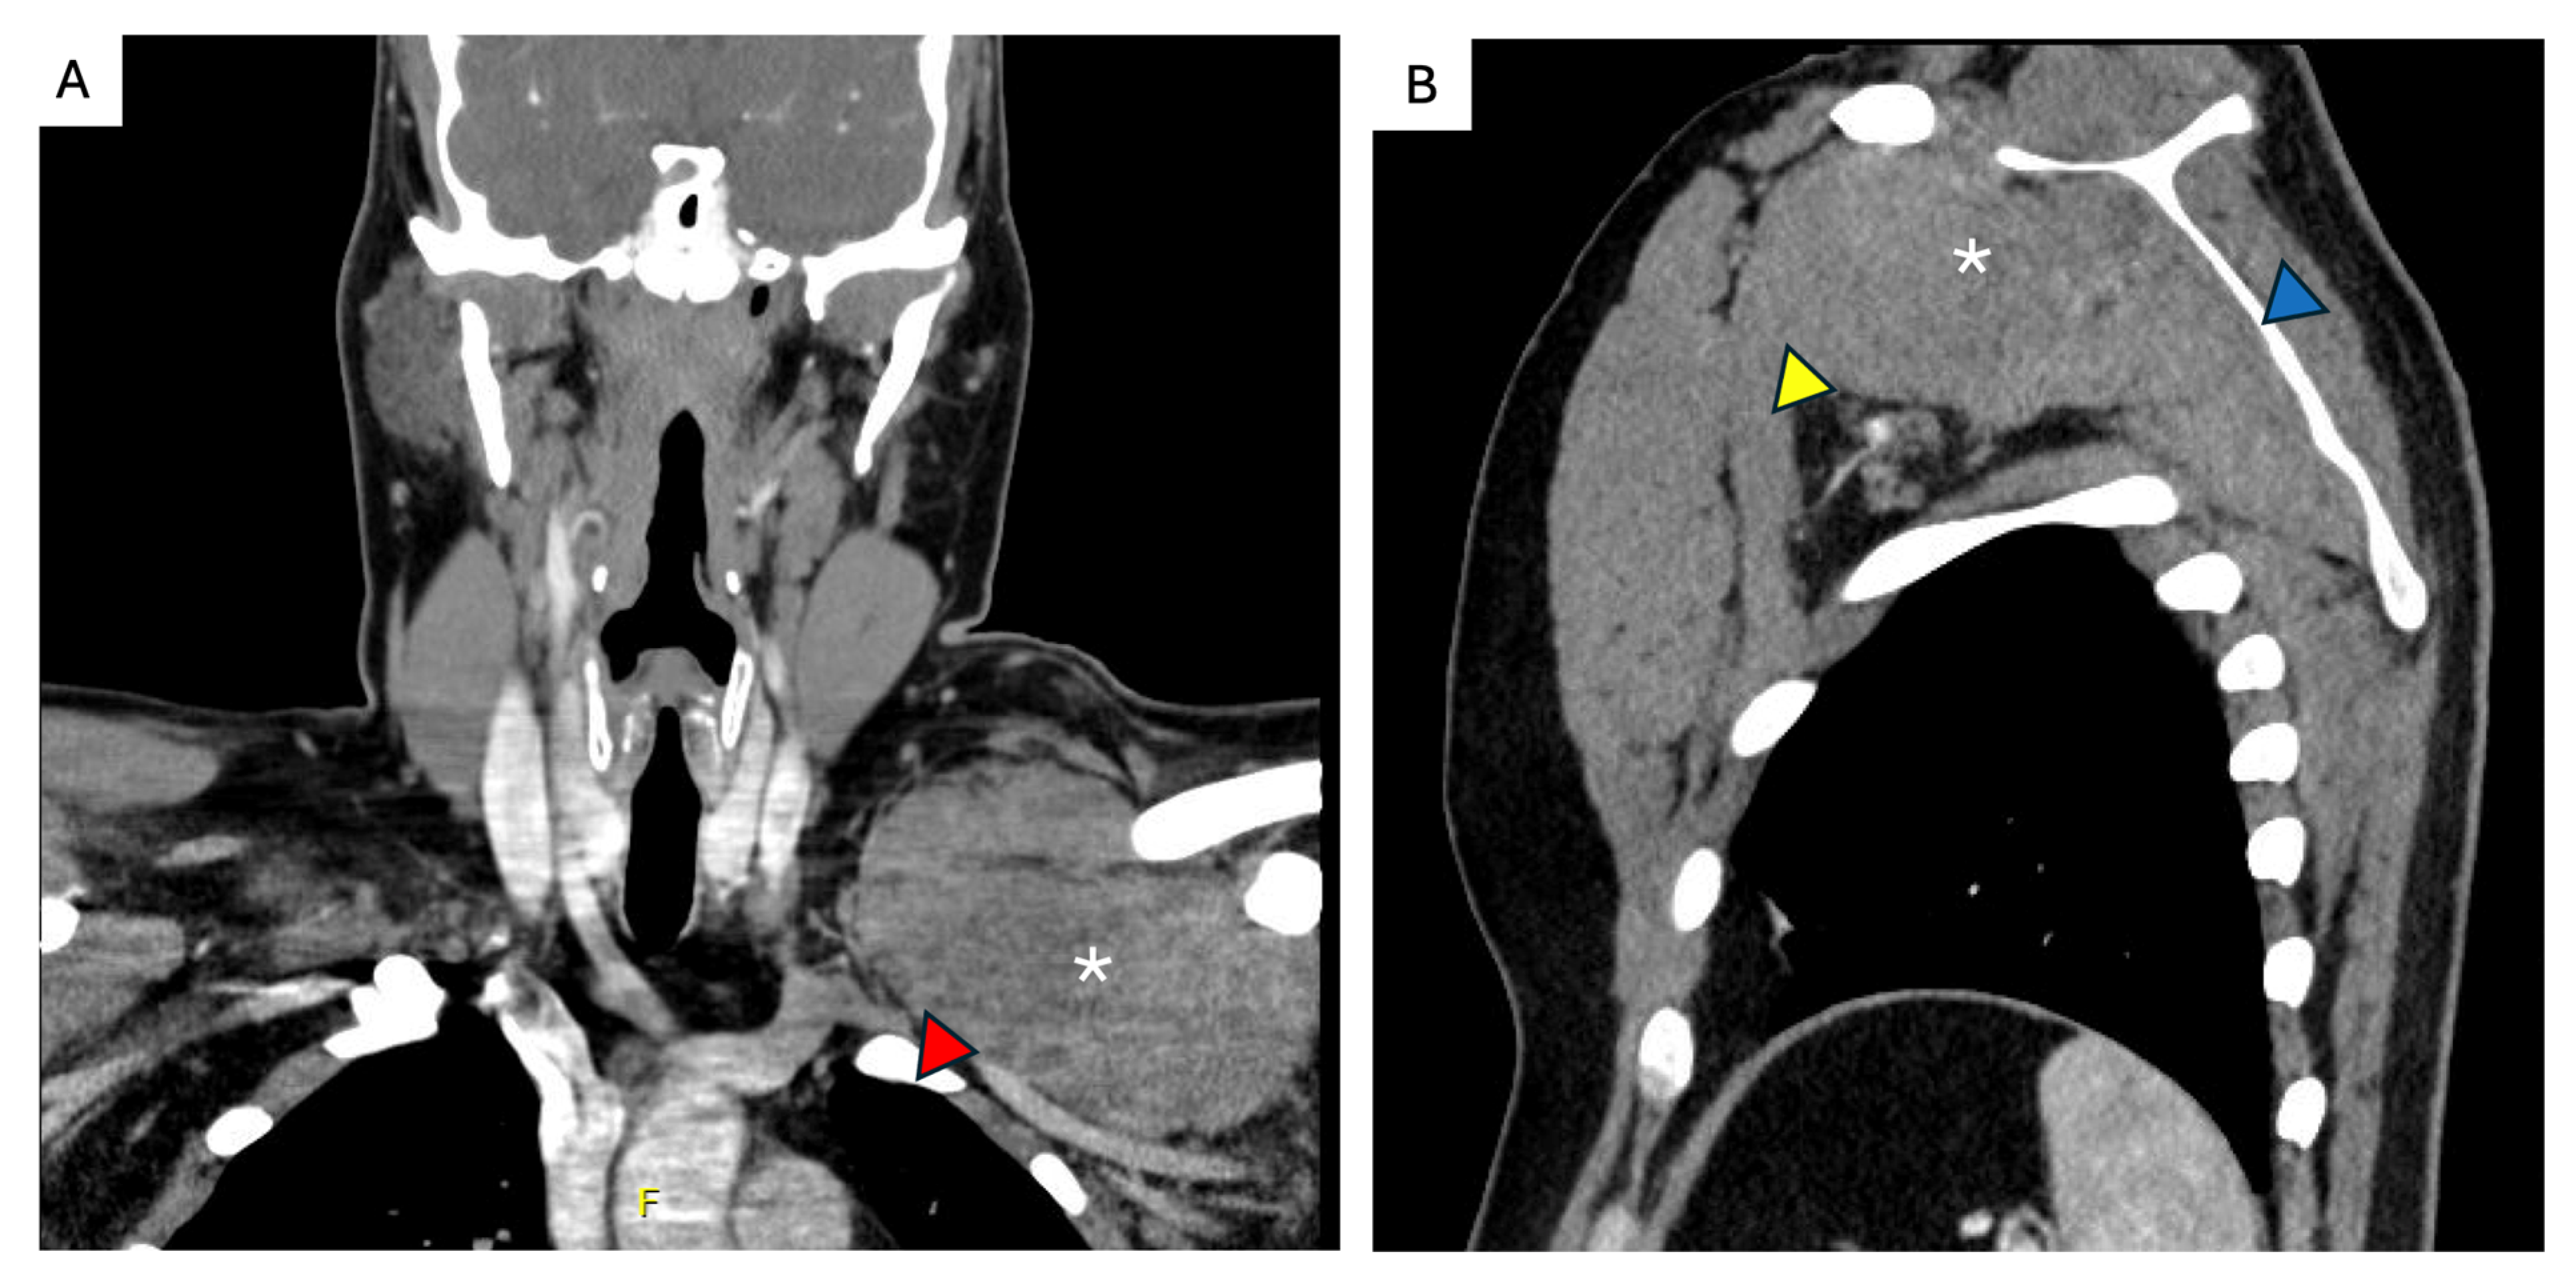

7. Unfavorable Locations

- Elective resection as primary treatment. In patients with resectable primary disease and low anticipated morbidity, complete macroscopic clearance can be achieved (Figure 3) with favorable operative outcomes in specialist centers [62]. When assessing resectability, key considerations include mesenteric vasculature involvement, anticipated length of small bowel and/or colonic resection, risk of short gut syndrome, and additional visceral involvement. The potential for future tumor growth and associated complications must also be carefully weighed [20,59]. In case of prior incomplete resection and evidence of residual disease, AS is recommended due to the possibility of an indolent course [63].